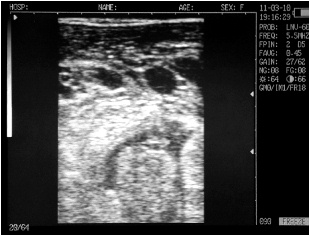

Ultrasound images of cows reproductive system, generated by a scanner Sonovet with rectal linear transducer.

Filled bladder cow